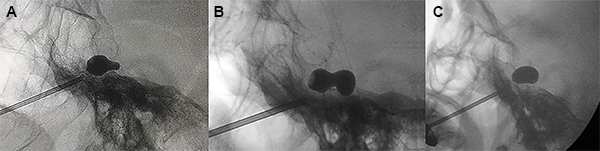

El balón con una jeringa de insulina previamente cargada con contraste radiológico (Iopamidol 612,4 mg /ml) fue lentamente insuflado usualmente entre 0.5 a 1 ml hasta obtener un balón en forma de pera (Figura 7A), o en reloj de arena en tamaño completo (Figura 7B). Se mantuvo insuflado por 60 segundos.

Figura 7: Formas de balón. (A) Pera, (B) Reloj de arena, (C) Oval.

La forma de pera indica que la punta del balón se encuentra dentro del poro trigeminal, que es donde debe estar para comprimir el nervio trigémino adecuadamente. Esta forma de pera correspondería a la anatomía interna de la cavum de Meckel y es indicador que está comenzando a sobresalir del cavum de Meckel hacia el poro trigeminal.

La forma de reloj de arena corresponde cuando la punta del catéter a atravesado parcialmente el poro trigeminal hacia la fosa posterior y el balón se infla parte dentro del cavum de Meckel y parte dentro de la fosa posterior. El término reloj de arena se asigna a formas en las que se identificó un istmo con un diámetro menor entre 2 partes redondas del balón con un diámetro mayor.

Cuando el balón es de forma oval (Figura 7C), redonda, elíptica o irregular, se desinfló el balón y la aguja fue retirada y reposicionada, inclusive se puede cambiar de catéter Fogarty hasta lograr la forma de pera o de reloj de arena, en caso de no ser posible por lo menos se debe lograr la forma oval. En estos casos generalmente se terminó insuflando entre 1.5 a 3 minutos.

La forma oval o redonda pueden aparecer debido a un cavum de Meckel grande, poca cantidad de contraste o una posición incorrecta de la punta del catéter. En la forma elíptica, el catéter está fuera del cavum de Meckel, en posición lateral infratemporal.